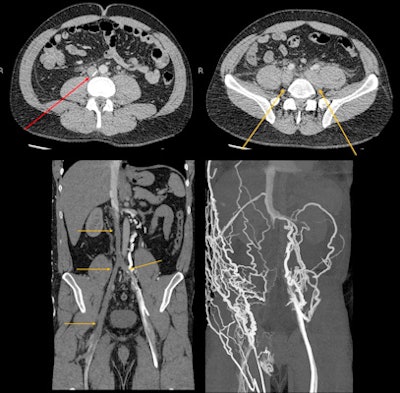

Pneumomediastinum has also been reported, and it relates to increases in intrathoracic pressure from drug inhalation and drug-related seizures. MDMA can also have a vasoconstrictive effect on the splanchnic vasculature. Multiple cases of gut ischemia associated with MDMA have been reported, as well as distal colon perforation from pressure necrosis due to constipation, they concluded.